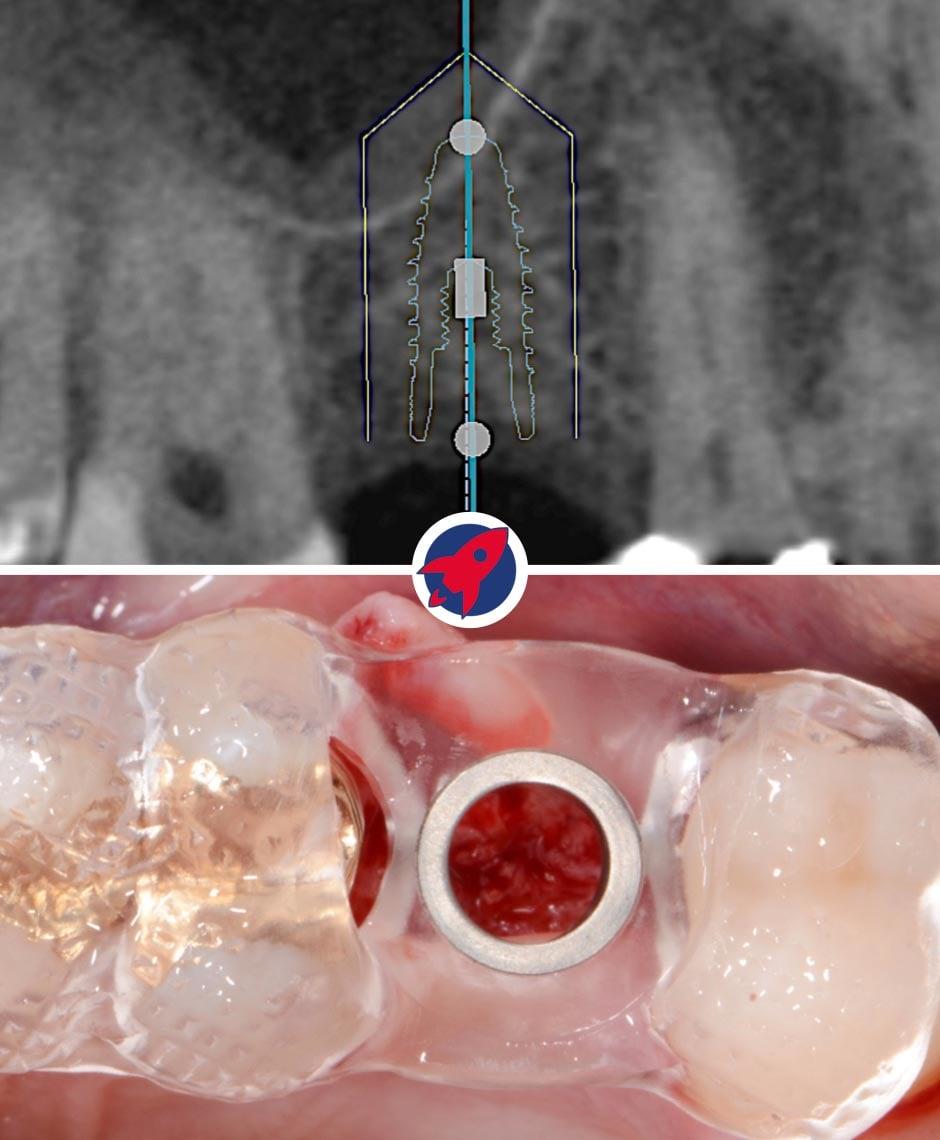

3D X-ray: Orthophos XG 3D

Safety begins with the right insight. Our Orthophos XG 3D provides us with a "transparent" view of your jaw. Unlike conventional 2D X-rays, we can see every anatomical structure in three dimensions. This allows us to plan procedures with millimeter precision and provide optimal protection for sensitive structures, such as nerve pathways.

The transparent jaw for your safety

High-resolution 3D images for precise planning and exceptionally gentle treatments.